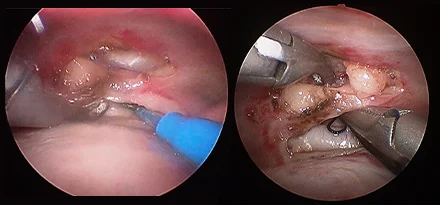

흉강경

복강경과 유사하게 최소 절개를 통해 흉강 수술을 진행하게 됩니다.

작은 구멍으로 카메라 포트가 진입하여 수술 부위를 시각화하고 진단과 치료를 진행할 수 있습니다.

흉강에서는 탐색과 조직생검을 통해 확실한 진단에 도움이 됩니다.

심낭수 치료를 위해 심낭막절제술, 최소침습 폐엽절제, 유미흉의 치료를 위한 흉관결찰(Thoracic duct ligation) 등이 진행될 수 있습니다.

흉강경심막절제술 (Preicardiectomy)

흉강경흉관결찰 (Thoracic duct ligation)